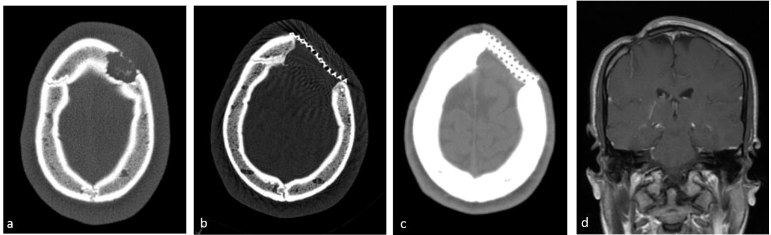

These procedures were performed under general anesthesia with intubation in the operating room. The lesion was removed and the surrounding abnormal bone tissue was sampled. During surgery, the neurosurgeon assessed for dural invasion. In earlier years a cranioplasty was performed as a second surgery and later on either cement or titanium mesh replaced the resected bone.

The median time between the biopsy request and procedure was 12 days (range 1–36 days). Surgical biopsy was diagnostic in all cases. Surgical interventions included resection in 24 cases and biopsy in 2 cases. Dural invasion was observed in only one instance. Bone replacement procedures were performed in 11 cases; one patient required a second operation for cranioplasty, 6 patients underwent cement replacement for skull defects, and 4 patients received mesh placement. Data were unavailable for 3 cases. The mean hospital stay following the procedure was 2.6 days (range 1–9 days), with 2 patients requiring intensive care on the first postoperative day.

Complications occurred in 14 patients (53.8%). Immediate postoperative complications occurred in 6 cases: three minor complications (two patients developed fluid collection at the site of resection, one with fever, another developed a hematoma at the surgical site) and three major complications (an infected titanium mesh, which was initially treated with antibiotics and later removed in a second operation, abscess at the surgical site, and a second surgery for completion of lesion resection in one patient). Late complications occurred in 8 cases and included headache in 2 patients, chronic sinusitis in one patient and esthetic cranial deformation in 5 patients. No anesthesia-related complications were reported.

In two FNB cases, on-site cytology yielded a diagnosis, facilitating rapid treatment initiation. These results are consistent with previous findings demonstrating the diagnostic value of on-site cytology in pediatric oncology. No complications occurred in the FNB group, whereas the surgical group experienced post-operative complications occurred in more than half of the patients (14/26), some major complications that necessitated a second surgery and prolonged hospitalization, and in 8 cases (30%) long standing complications including chronic headache, chronic sinusitis and in 5 cases deformation of the skull. The surgical group also exhibited a higher rate of bone defect repair, with titanium mesh and cement replacement being used in some cases. The current consensus recommends biopsy over resection for lesions larger than 5cm to avoid unnecessary enlargement of the bony defect and complications such as delayed healing or permanent skeletal deformities. For lesions between 2–5cm, biopsy combined with partial curettage is an acceptable option. Anesthesia-related complications were not reported in either group.